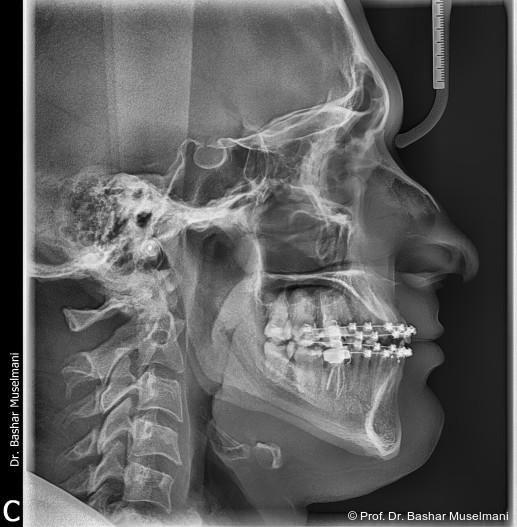

Fernröntgenologische Befunde (Behandlungsbeginn)

• SNA: 81,5°

• SNB: 84,3°

• ANB: −4,9°

• Wits-Wert: −8,4 mm

Während des Behandlungsverlaufs wurden ein Kontroll-Fernröntgenseitenbild sowie ein Orthopantomogramm angefertigt.

Fernröntgenologische Befunde (Zwischenkontrolle)

• SNA: 81,9°

• SNB: 83,9°

• ANB: −2,1°

• Wits-Wert: −2,0 mm

Fernröntgenologische Befunde

Initial

• ANB: −2,9°

Zwischen

Ende

• SNA: 82,0°

• SNB: 81,5°

• ANB: 0,6°

• Wits-Wert: +0,7 mm

Zusammenfassung der sagittalen Veränderungen

• SNA (maxillare Position): leichte Zunahme von 81,5° auf 82,0° → maxillare Position blieb nahezu stabil.

• SNB (mandibuläre Position): Abnahme von 84,3° auf 81,5° → retrusive Tendenz des Unterkiefers.

• ANB (Relation Ober- zu Unterkiefer): Zunahme von −2,9° auf 0,6° → deutliche Korrektur der Klasse III-Relation hin zu neutraler Okklusion.

• Wits-Wert: Verbesserung von −8,4 mm auf +1,7 mm → klinisch stabile sagittale Okklusion erreicht.

Interpretation

Die Behandlung führte zu einer signifikanten Korrektur der Klasse III-Fehlstellung durch retrusive Unterkieferposition und leichte Anpassung der Maxilla, was in einer nahezu normalen sagittalen Kieferrelation resultierte.